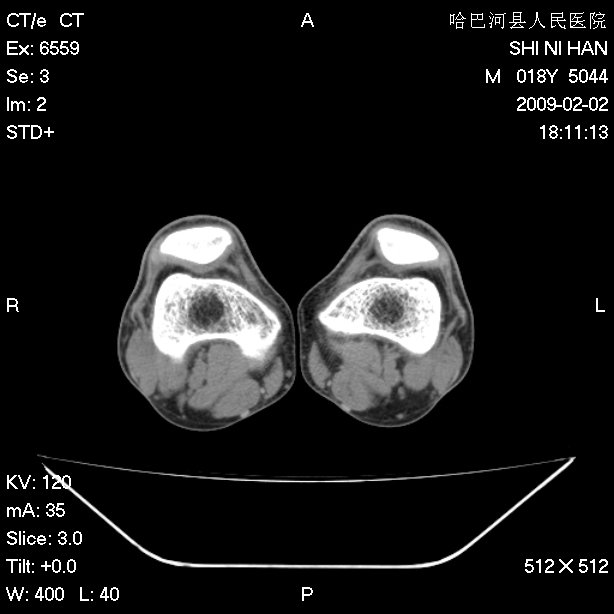

标题: CT17889:外伤后右膝关节反复疼痛3年余 [打印本页]

标题: CT17889:外伤后右膝关节反复疼痛3年余

ct未见明显异常。关节腔未见明显积液,半月板未见明显撕裂。但最好还是mri看看韧带及半月板情况。